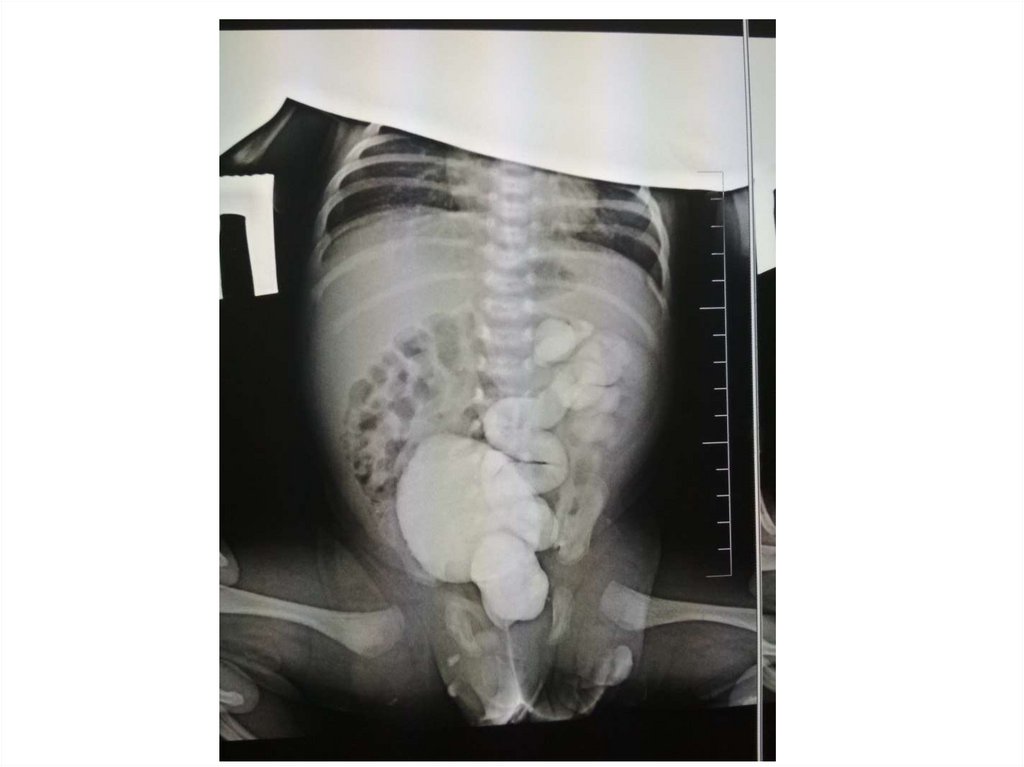

Обзорная рентгенограмма органов

брюшной полости

Рентгеноконтрастные

конкременты в

проекции правой

почки